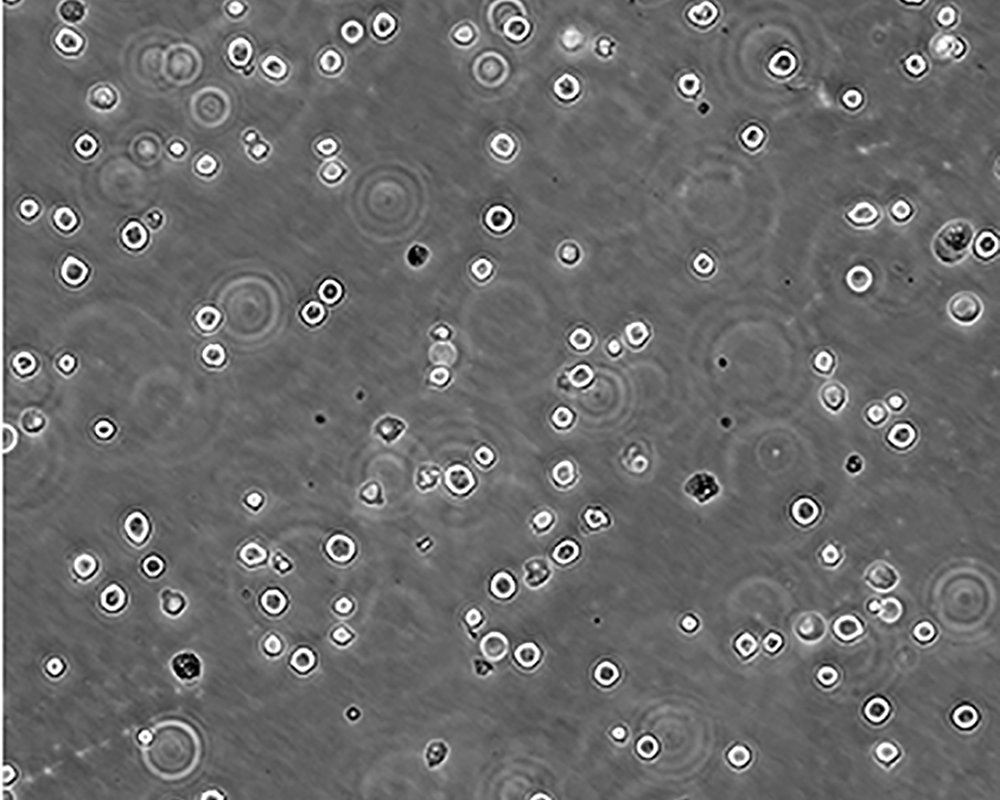

K-562 [K562]細胞

產品名稱 K-562 [K562]細胞

中文名稱 人慢性髓原白血病細胞

組織來源 慢性髓細胞白血病;女性

生長特性 suspension

形態(tài)特征 lymphoblast

細胞描述 The cell population has been characterized as highly undifferentiated and of the granulocytic series. Studies conducted by Anderson, et al. , on the surface membrane properties led to the conclusion that the K-562 was a human erythroleukemia line. K-562 blasts are multipotential, hematopoietic malignant cells that spontaneously differentiate into recognizable progenitors of the erythrocytic, granulocytic and monocytic series. The effect of inducers on sublines derived from the original K-562 cell line have been reviewed by Koeffler and Golde. Karyological studies on various K- 562 sublines have been classified into three groups(A,B,C) by Dimery, et al. The strain obtained by the ATCC most closely resembles the B population. Occurrence of the Philadelphia chromosome, however, was of much lower frequency; none detected in 15 metaphases examined. The line is EBNA negative.